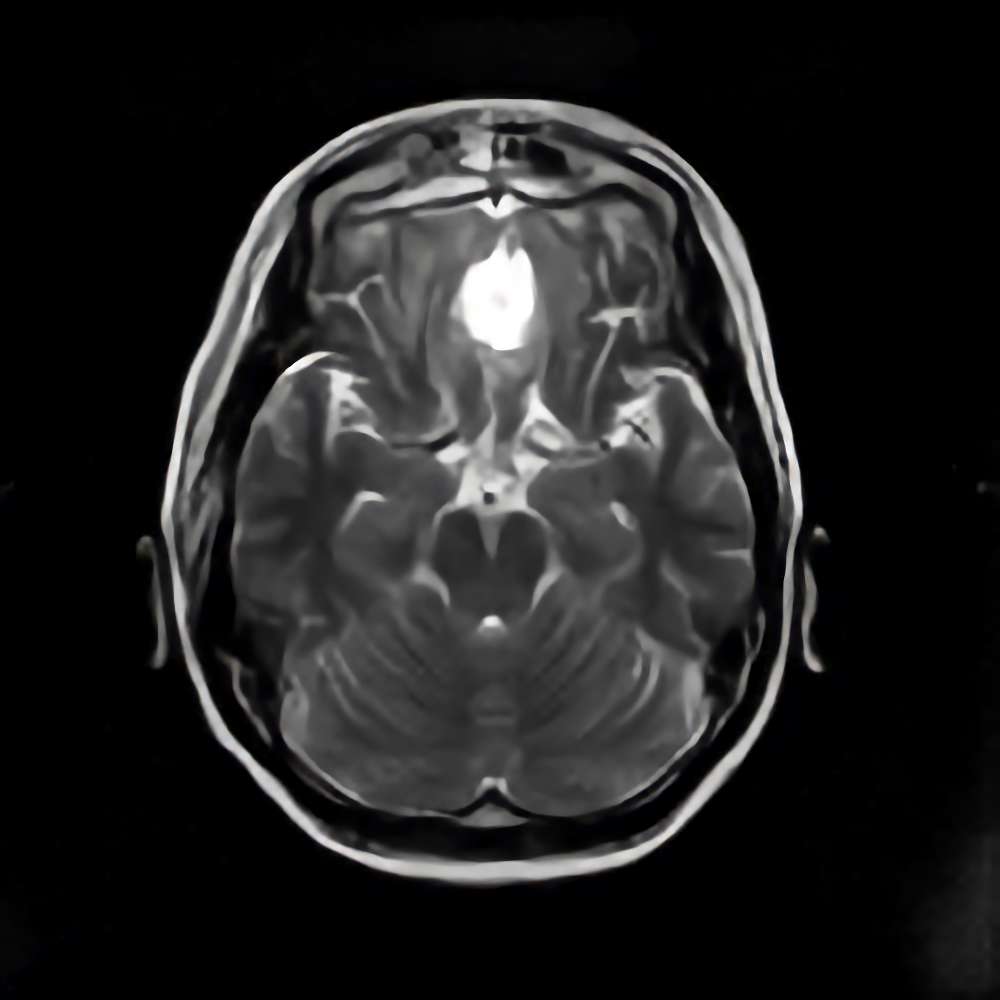

No.’21_27 手術前1

No.’21_27 手術前2